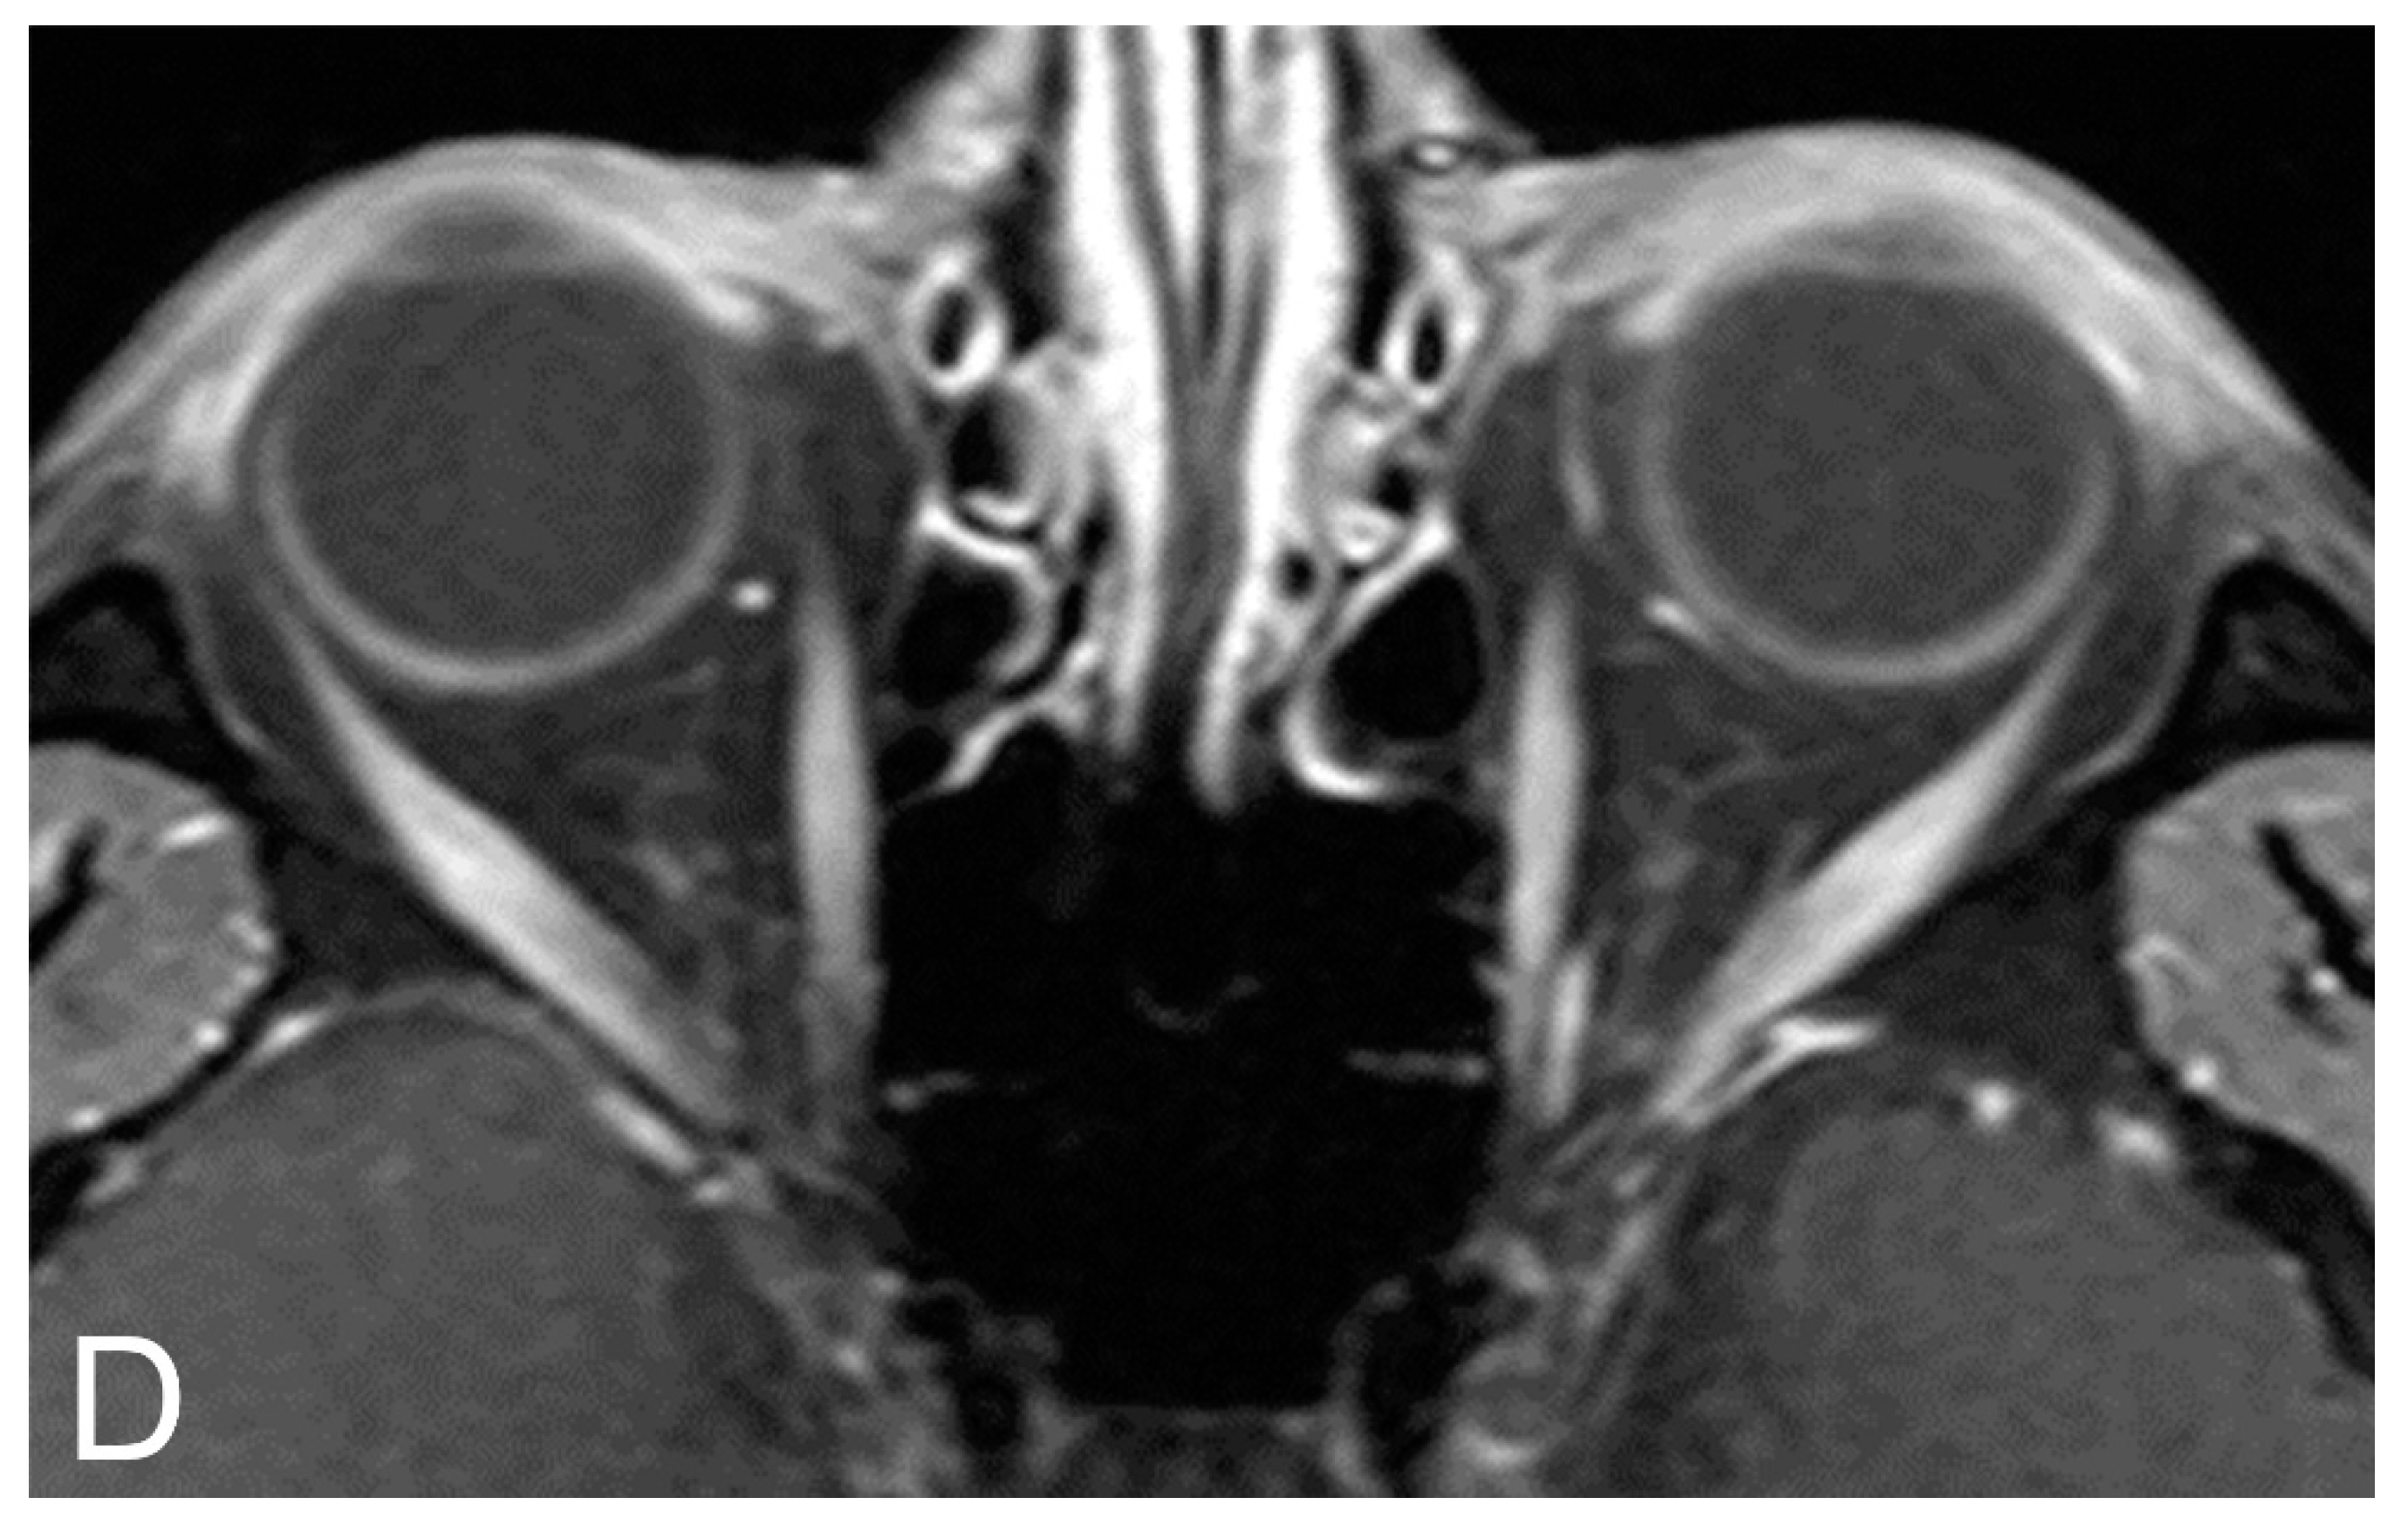

5.2. Magnetic Resonance Imaging (MRI)

5.3. MRI Correlation with Disease Severity